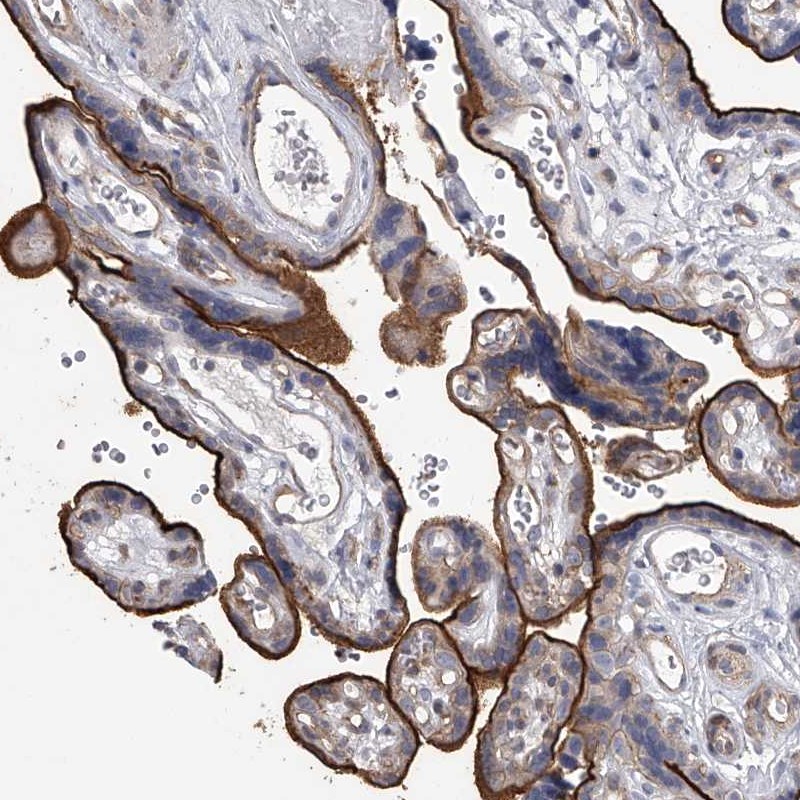

Immunohistochemical staining of human placenta shows strong membranous positivity in trophoblastic cells.